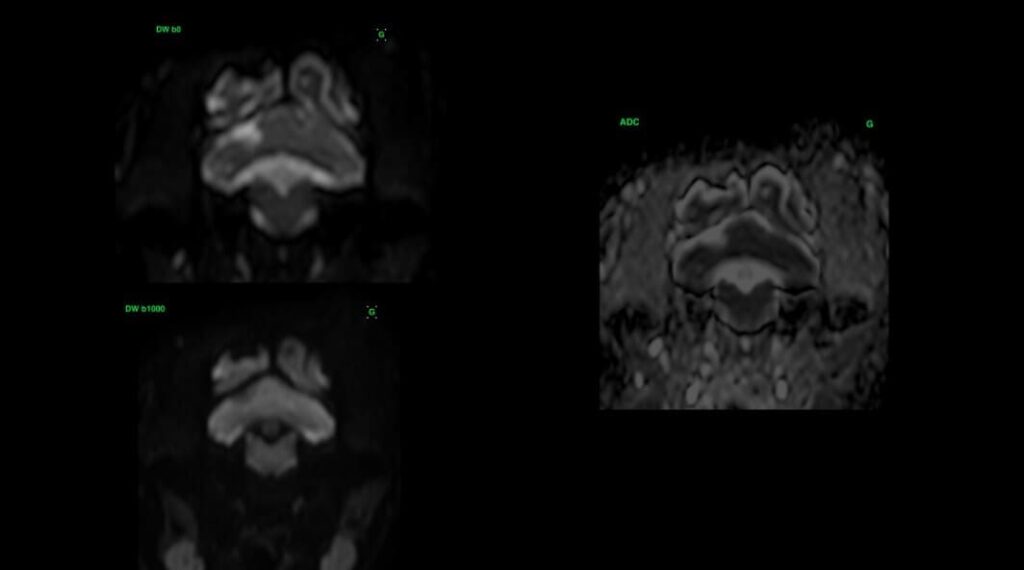

L’IRM est l’imagerie de choix pour ces lésions ischémiques. Les lésions aigues apparaissent hyperintenses sur les séquences T2 et T2 FLAIR, hypointense en pondération T1, et ne montrent pas de rehaussement. L’imagerie en diffusion permet une détection plus précoce de ces lésions. Elle permet également une estimation de l’âge de la lésion et de la taille du noyau infarcié. Les lésions aigues présentent une restriction du signal de diffusion, et apparaissent hyperintense sur la séquence DWI, et hypointenses sur la carte ADC. Les valeurs sur la séquence ADC sont diminuées pendant 4-5 jours, se normalisent entre 4 et 10 jours, et réaugmentent après 10 jours. Ces lésions ne créent pas d’effet de masse, sauf en cas d’œdème vasogénique associé, à son maximum 3-4 jours après l’apparition de la lésion. On peut parfois observer un rehaussement périphérique de la lésion pendant la phase de rupture de la barrière hématoméningée.

Cas clinique 1 – Scanner de « Isis » – lésion ischémique subaiguë dans le territoire de l’artère cérébrale moyenne